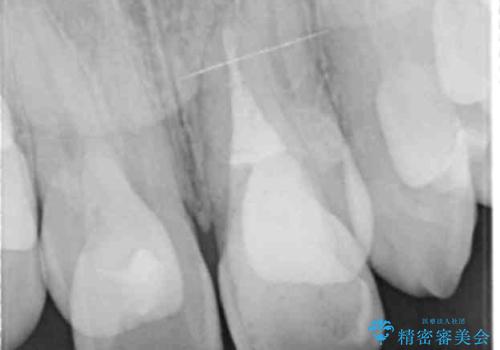

- 前歯が黒くなってきたことを主訴に来院された患者様です。

精査したところ、う蝕により歯の内側から黒くなっていました。

根管治療後、セラミッククラウンによる補綴を行いました。

※う蝕が大きく健全歯質が非常に薄いため、長期的予後に関しては不明であることをご理解頂いた上で治療を行いました。